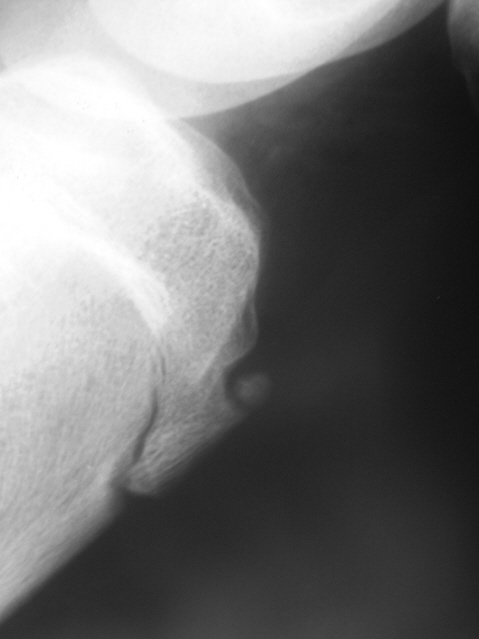

Уважаемый Валентин Львович! Я не сомневаясь, расценю данную картину, как остеохондропатию бугристости большеберцовой кости, болезнь Осгут- Шляттера. Имеется фрагментация бугристости (как у Рейнберга)

Я бы здесь поставила Осгуд-Шлаттера, картинка как из книжки. Но надо еще ориентироваться и на клинику.

При наличии клиники и мягкотканного компонента в хондропатии можно не сомневаться.

Большое спасибо коллеги за высказанные мнения. А вариантом нормы "сие" может быть?

Рискну предположить, что может. Впрочем, это косвенно подтверждают и коллеги:

В.Б.Серов: "При наличии клиники и мягкотканного компонента..."

Ola-la: "Но надо еще ориентироваться и на клинику"